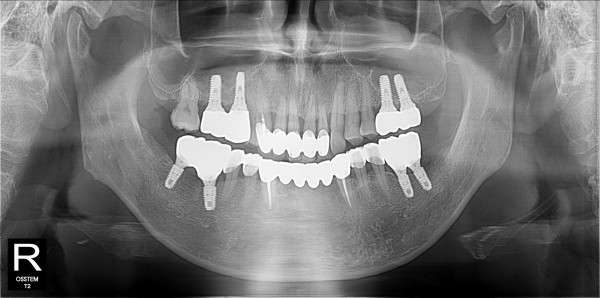

구치부 임플란트 최고관리자 0건 23-11-07 18:32 본문 구치부 임플란트 + 전치부 크라운 목록 이전글구치부 임플란트 23.11.07 다음글구치부 임플란트 23.11.07 댓글목록 0 댓글목록 등록된 댓글이 없습니다.